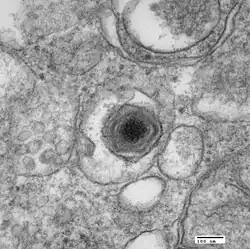

African swine fever virus